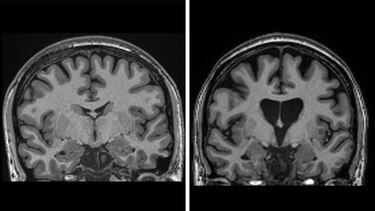

También muestran que el tratamiento está salvando células cerebrales.

Los niveles de neurofilamentos en el líquido cefalorraquídeo, un claro indicio de la muerte de las células cerebrales, deberían haber aumentado en un tercio si la enfermedad hubiera seguido progresando, pero en realidad eran más bajos que al inicio del ensayo.